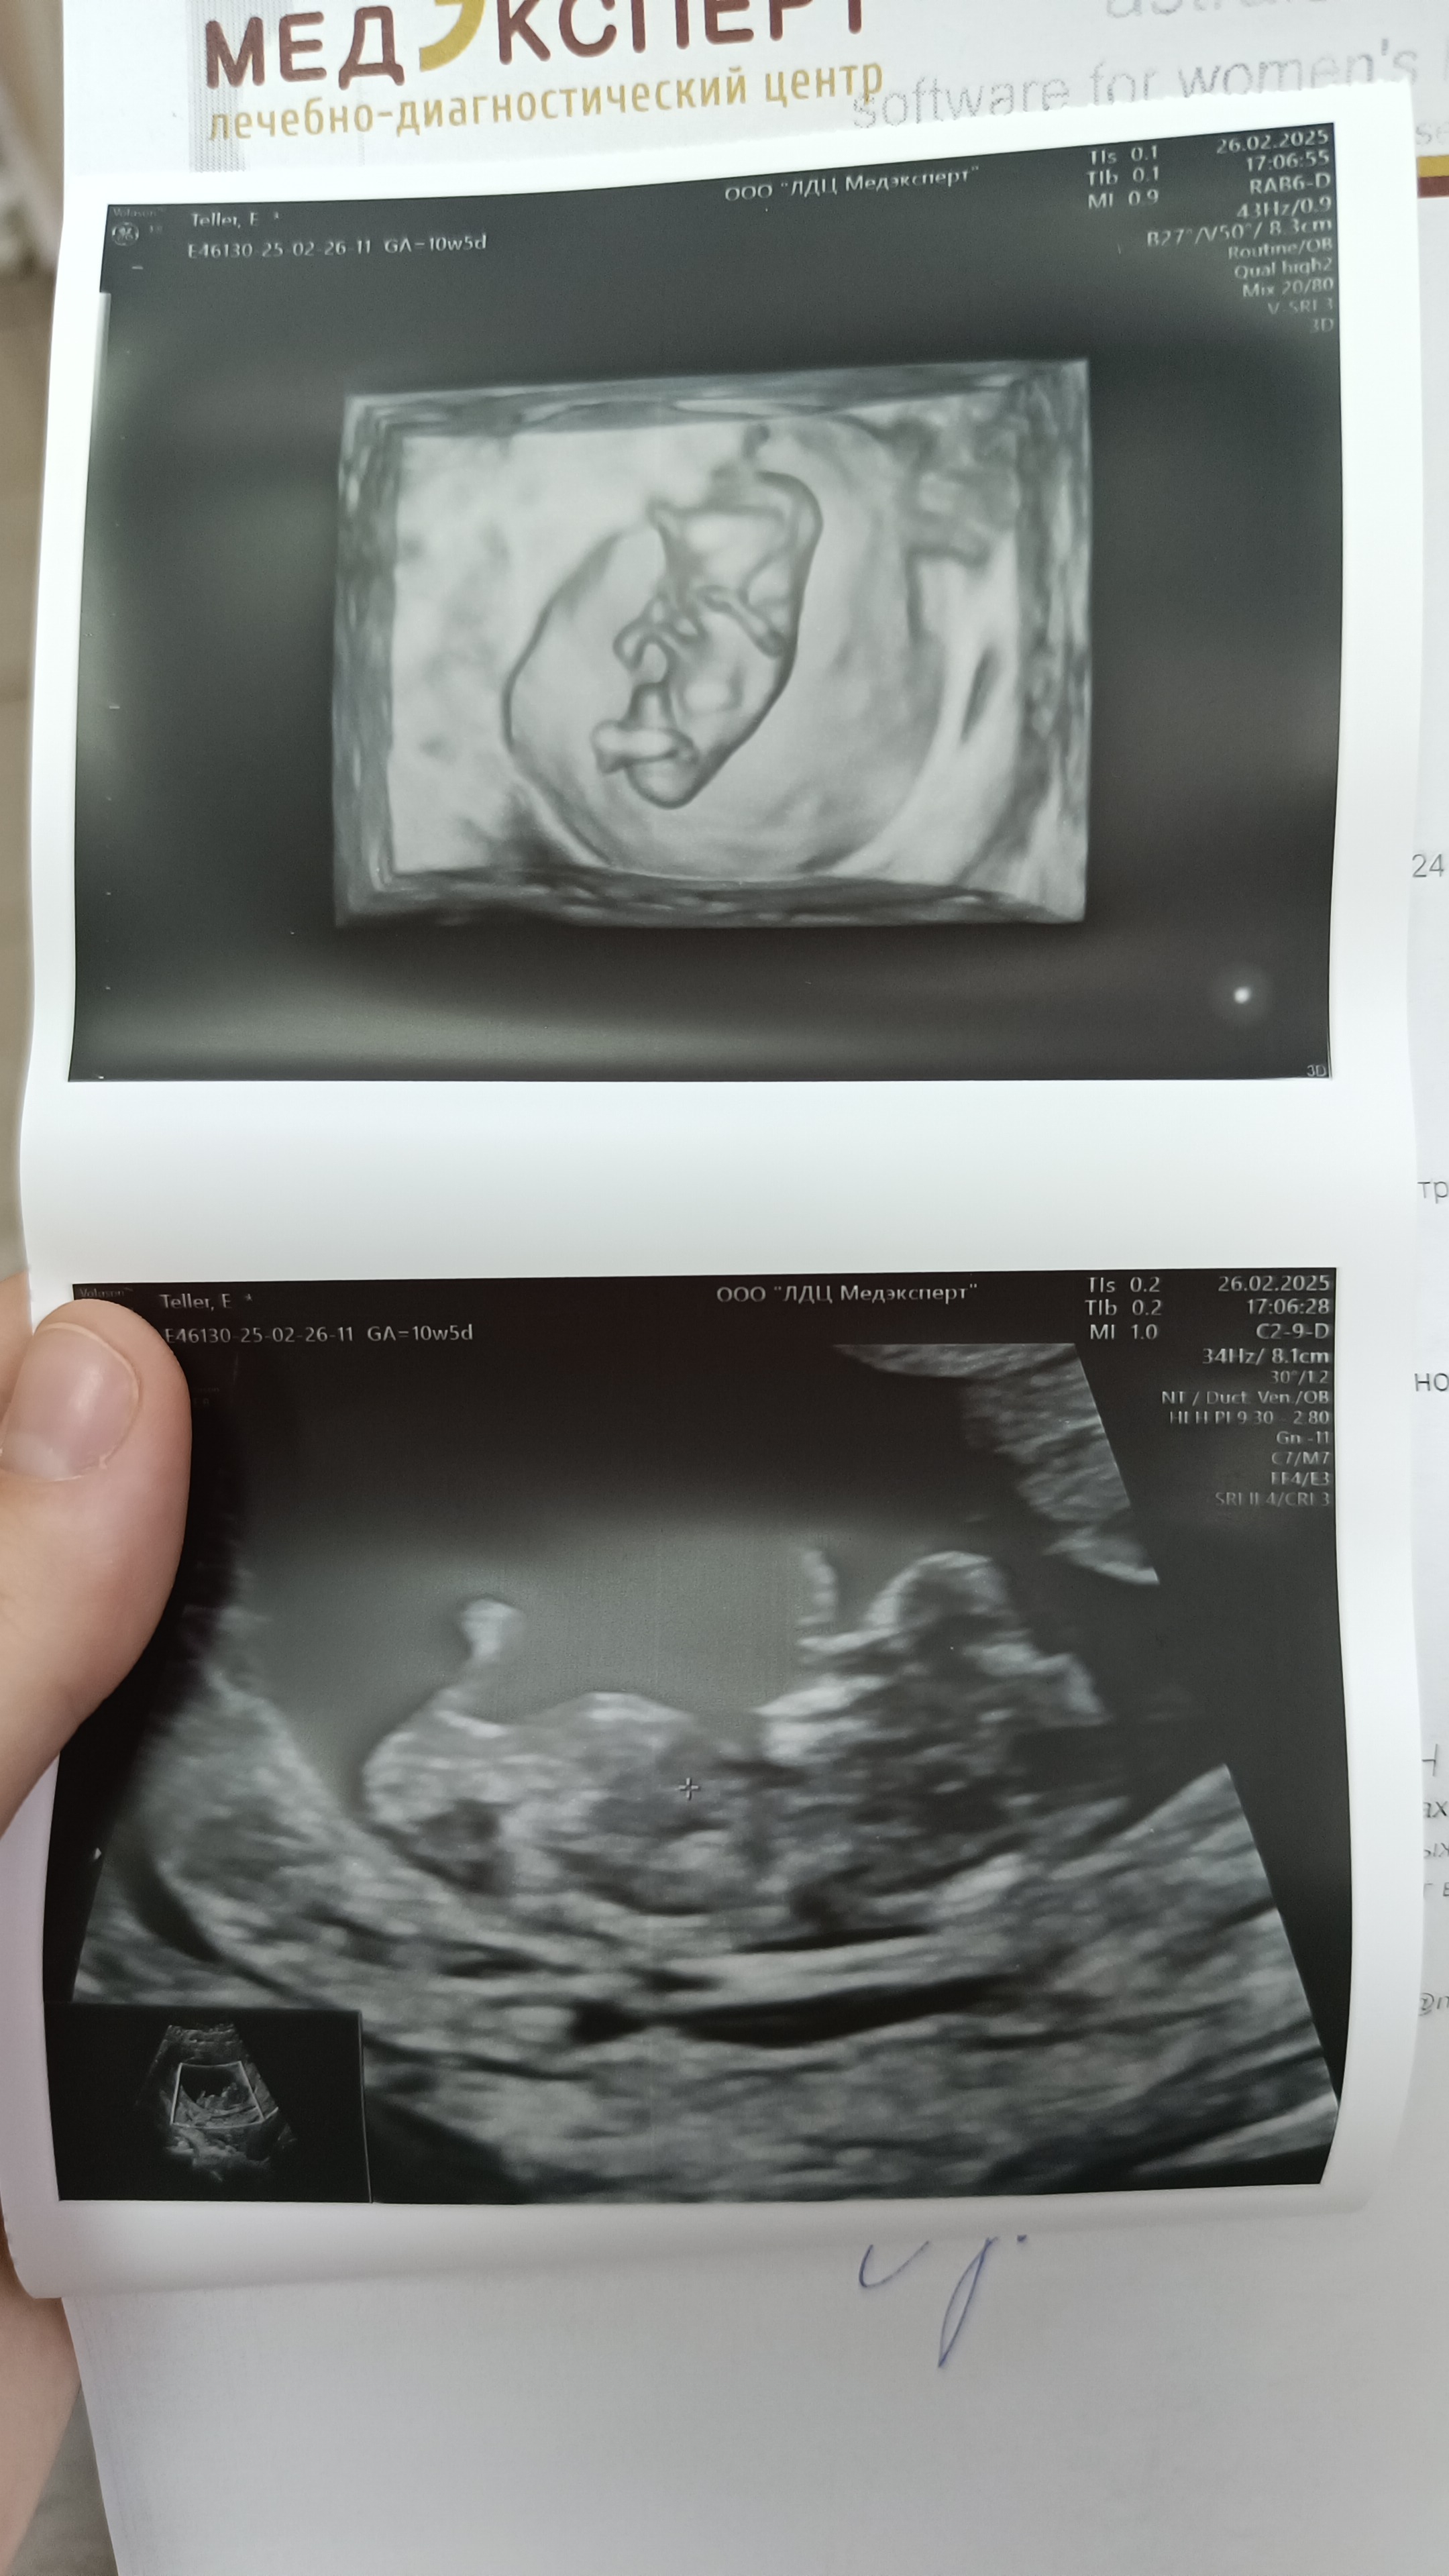

10н и 5 дней и пупочная грыжа..

УЗИ

Гематома ушла, но пришла новая проблема 🫠

Хотя врач и сказал, что это норма на этом сроке беременности боюсь жутко.